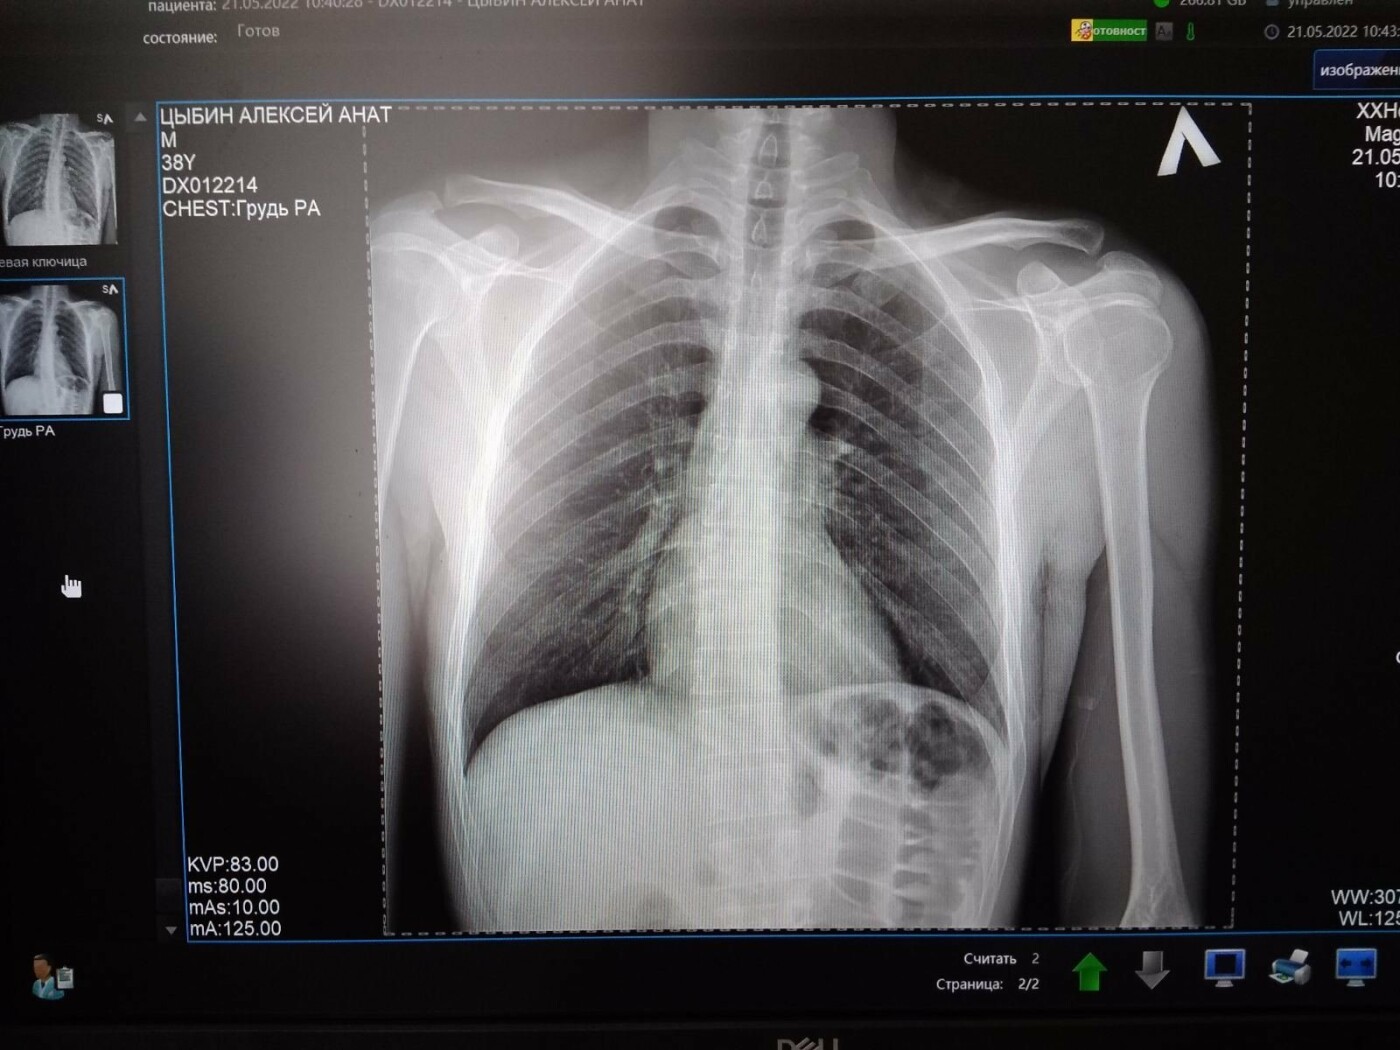

Також Олександр повідомив, що в результаті аварії велосипедист отримав серйозні пошкодження – розрив ключиці. Тепер постраждалий потребує операції та довгої реабілітації.